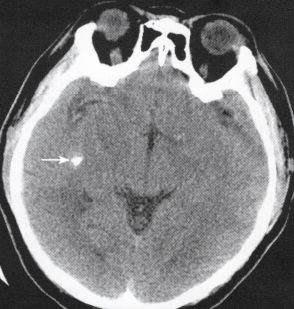

李文录,男,52岁,左侧大脑中动脉动脉瘤